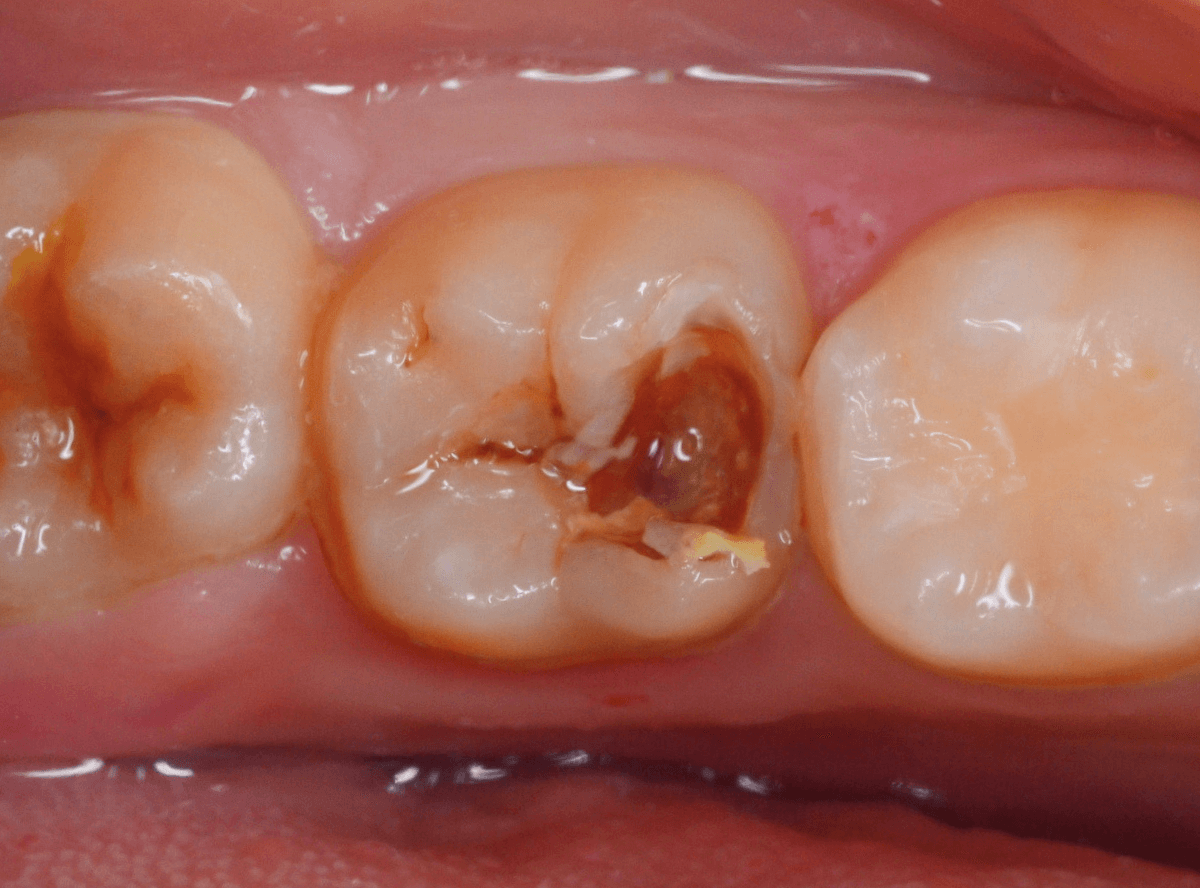

Case.12 検診で見つかった、インレーの下の深い虫歯

検診目的で来院された患者さんです。

特に気になるところもなかったですが、検査をすると、お口の中の色々な部分に虫歯が見つかりました。

その中の一か所、上の奥歯のインレーの下の虫歯です。

見た目だけでははっきりわかりませんでしたが、レントゲン写真で確認すると、インレーの下で虫歯になっているのがわかります。

インレーを除去して、治療を開始します。

ある程度、虫歯を除去したところで、う蝕検知液で確認します。

赤い部分が虫歯です。

やはり、レントゲン写真で確認した部分が深めの虫歯になっていたようです。